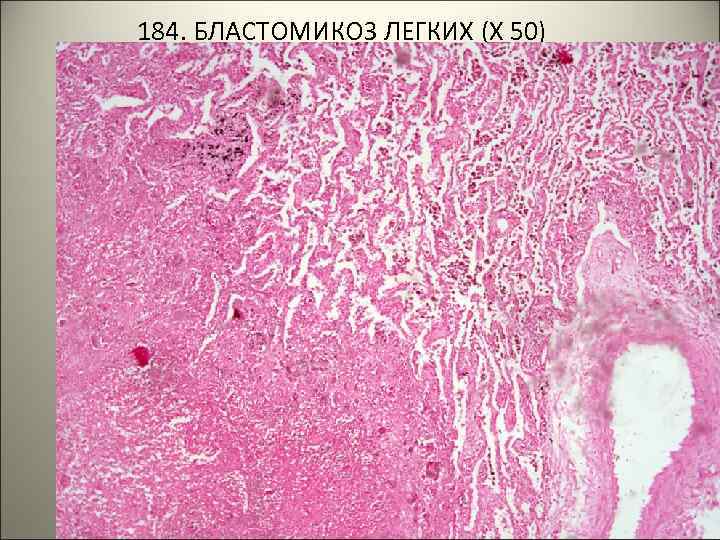

• 184. БЛАСТОМИКОЗ ЛЕГКИХ. • В ткани легкого очаги некроза и продуктивное воспаление с большим количеством гигантских клеток инородных тел, содержащих грибы черного цвета • УКАЗАТЬ НА РИСУНКЕ: • 1 – некроз • 2 – продуктивное воспаление • 3 – гигантские клетки • 4 – грибы.

184. БЛАСТОМИКОЗ ЛЕГКИХ (Х 50)

184. БЛАСТОМИКОЗ ЛЕГКИХ (Х 1000)